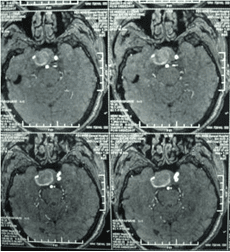

顱內(nèi)動脈瘤是指腦動脈的局部性異常擴大,多在腦底動脈的分叉處或分支的夾角向外突出,多呈囊狀。TCD對顱內(nèi)動脈瘤的總檢出率為67 %,動脈瘤>1cm的檢出率為82 %。TC D 對較大動脈瘤的檢測有其特征性表現(xiàn),其典型表現(xiàn)為:瘤體內(nèi)血流速度明顯低于載瘤動脈血流速度,其收縮峰陡峭或多峰不整,舒張期末流速極低或斷流,PI 值增高,多為雙向血流,聲頻低鈍,似撞擊樣轟鳴音。

經(jīng)顱多普勒

頸內(nèi)動脈虹吸段巨大動脈瘤(約3cm ×3cm

TCD 檢查顱內(nèi)動脈瘤,可以了解動脈瘤部位,大小,瘤體內(nèi)血流,頻譜特征,脈動指數(shù),載瘤動脈血流速度等。其作為一種無創(chuàng)的腦血管病檢查手段,它摒棄了傳統(tǒng)腦血流圖的不準(zhǔn)確性和腦血管造影的有創(chuàng)性,亦為CT MRI 等現(xiàn)代影像技術(shù)提供了腦血管血流動力學(xué)參數(shù),成為影像診斷的重要佐證,利于病情隨診和篩選患者,因而對腦血管病診斷、療效評估有重要價值,也是腦血管病血流動力學(xué)研究不可缺少的設(shè)備之一。